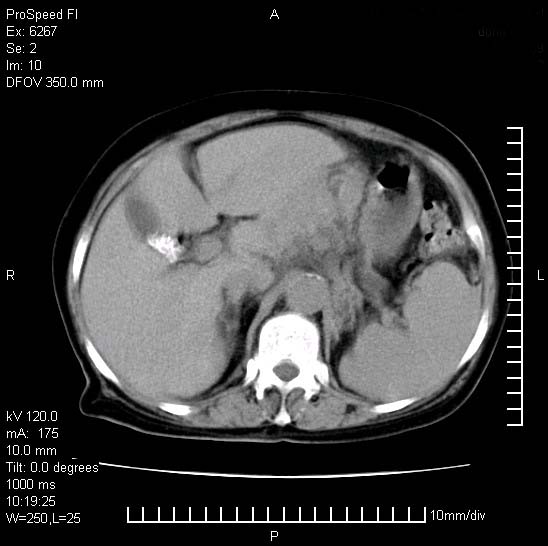

患者糖尿病,腹痛,恶心,呕吐。黄疸,意识较差,血糖很低(数值不详),临床以胆囊,胆管炎,低血糖反应收治。看的腹片少,各位帮忙看看,胰腺有问题吗??

胆囊炎,胆石症;胰腺炎可以确定,但需要增强,除外肿瘤

1.胰腺体积增大,胰周脂肪间隙消失,胰腺炎可以确定。必要时实验室进一步检查。

2.胆囊炎,胆石症。

胰腺体积增大,胰周脂肪间隙消失,考虑胰腺炎。胆囊炎,胆石症。

脾大,原因?胆结石;胰腺肿大,边缘模糊,建议查定性指标血尿淀粉酶,除外胰腺炎

考虑胰腺炎。胆囊炎,胆石症。脾大。